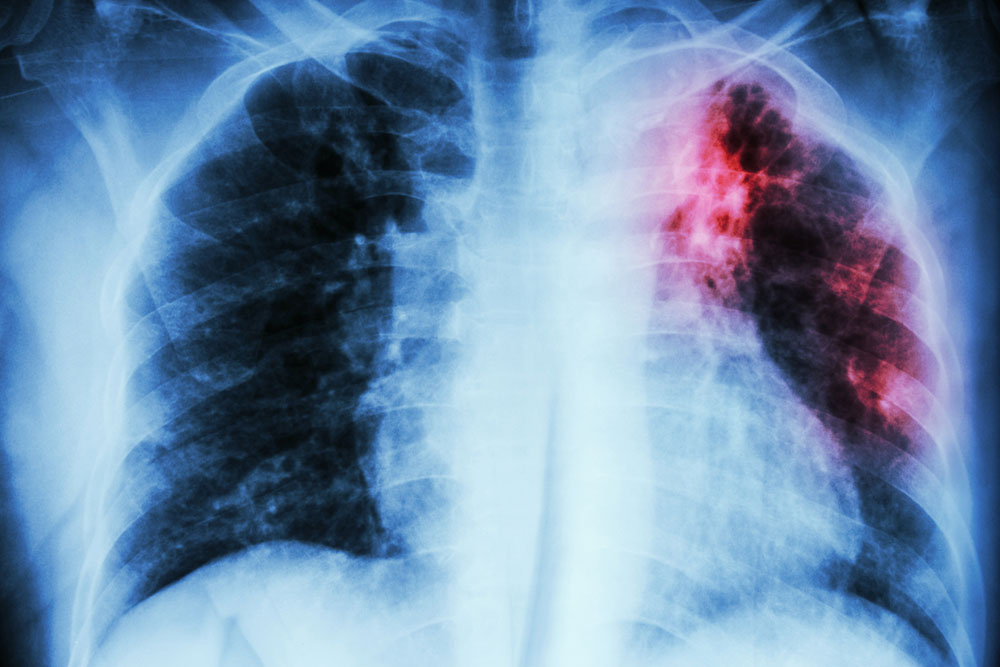

It is an ultrasound test for the heart. - Chest X-ray

This non-invasive technique provides a clear and detailed picture of your heart and lungs which the doctor can examine to detect any problem. - Computerized Tomographic Angiography